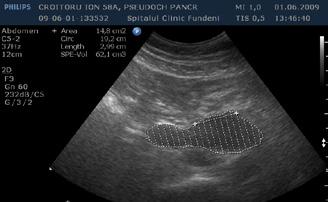

A opera sau a nu opera? Raspunsul ecografistului

Dr. Dan Adrian Stănescu 24